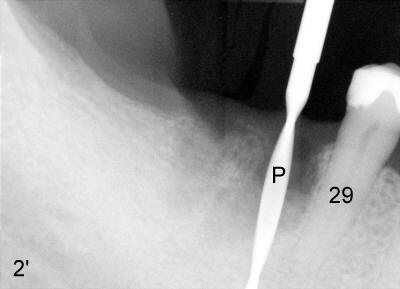

When 2.0 mm pilot drill was placed at ~ 17 mm (Fig.2': P), it is not parallel to the long axis of the tooth #29. Effort was exerted to place the next tapered drill (2.5x17 mm) in the right trajectory (Fig.2). The black line indicates the length of the drill (17 mm). Return to main text